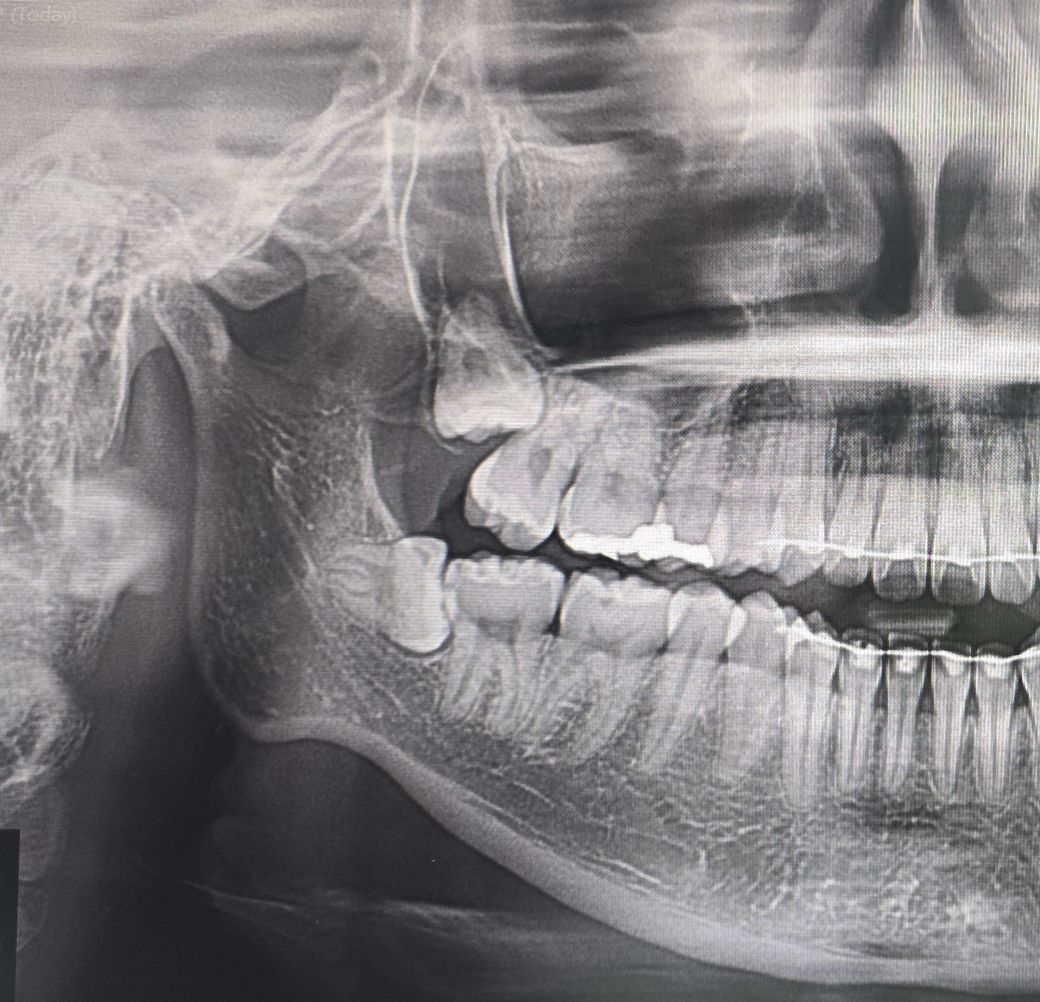

윗사랑니발치 블로그들 보는데 사랑니끝부분이 어금니 뿌리에 있는건 몇몇 봤는데 사랑니 뿌리가 저만큼 위쪽에 있는 경우는 없더라구요

가로로 긴 하얀선이 콧구멍 부분인거 같은데 반이나 넘게 선 위에 있네요 이러면 상악동천공은 100퍼센트인가요?

근데 뺄수는 있는걸까요? 엄청 위에 있는거같은데

엑스레이 사진과 같은 위쪽 사랑니의 경우 뽑기 조금 어려울 수도 있습니다 뺄수야 있겠지만 기본적으로 상악동 천공 가능성도 있고, 뼈를 좀 쳐야할 것 같습니다